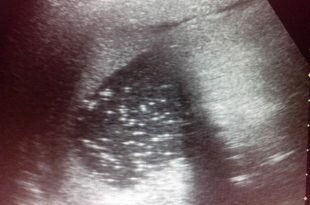

Важность печени заложена в ее функционале, благодаря которому поддерживается работоспособность других органов и систем, поэтому любые патологии железы чреваты серьезными нарушениями с ухудшением общего состояния человека. Помимо распространенных печеночных заболеваний (цирроз, дистрофия, рак), существуют недуги, встречающиеся с меньшей вероятностью, но оттого не менее опасные. Речь идет об энцефалопатии, когда повышается концентрация аммиака из-за потери печенью метаболической способности по отношению к белкам (состояние чревато путаницей сознания, комой), портальной гипертензии, провоцирующей развитие варикоза внутренних органов, увеличение селезенки (вплоть до инфаркта).